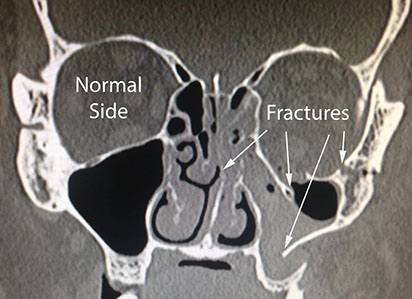

Midface fractures that need operative repair